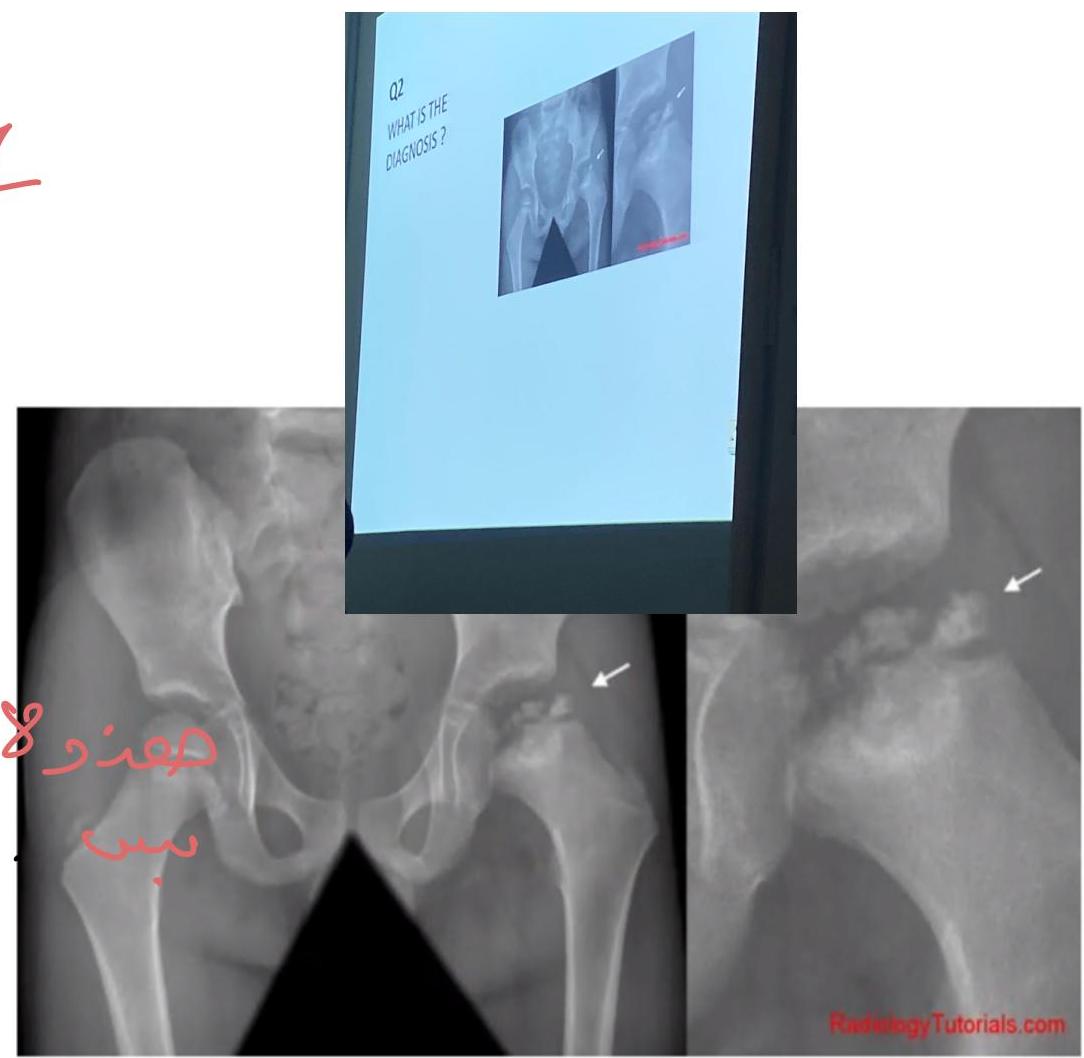

Perthes Disease

Diagnosis:

- Perthes disease (Legg-Calvé-Perthes disease)

Cause:

- Avascular necrosis of the femoral head (appears as a “broken” or flattened end of the femur)